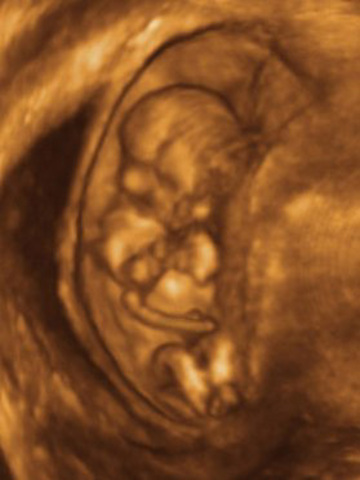

• 9 weeks

9 weeks

squints, swallows, moves tongue, makes fist